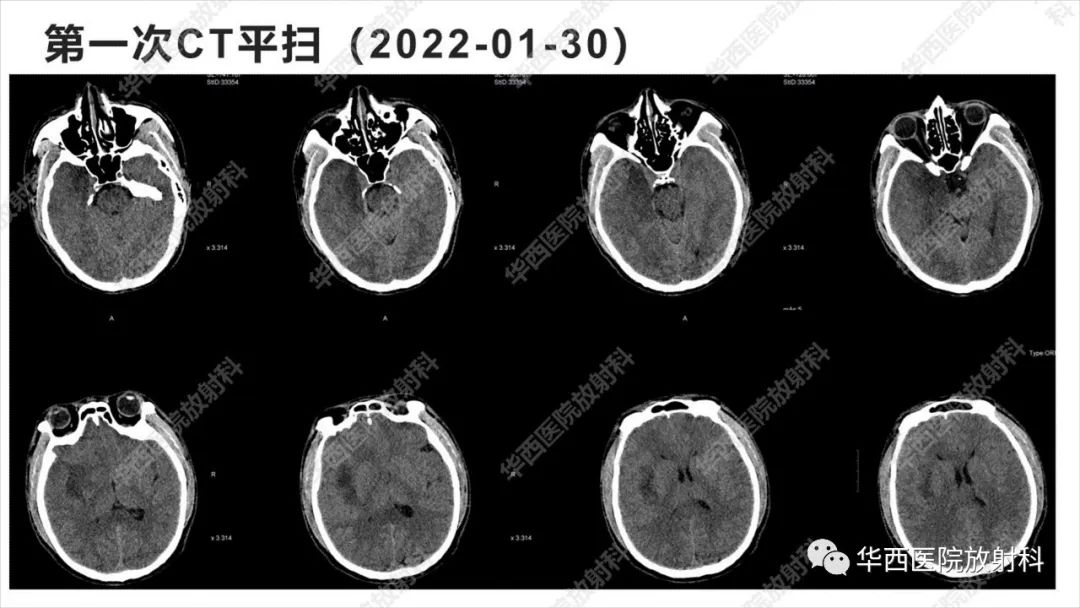

【病例】出血坏死性病毒脑膜脑炎1例CT及MR影像学表现和鉴别诊断-1